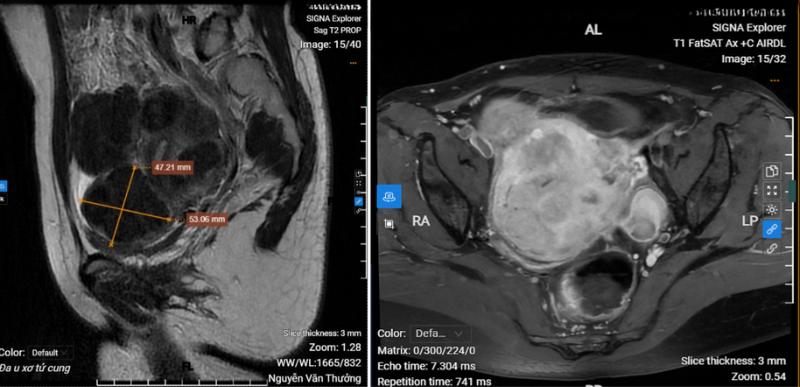

.png)

Chụp MRI vùng tiểu khung cho thấy hình ảnh đa u xơ tử cung

MRI vùng tiểu khung cho thấy tử cung có nhiều khối u xơ (khối u lớn nhất có kích thước 47x53mm), được xếp loại từ L2 - L6. Đây là phân loại dựa trên vị trí u xơ theo hệ thống FIGO (International Federation of Gynecology and Obstetrics):

- L2: u xơ dưới thanh mạc có <50% thể tích nằm ngoài tử cung;

- L3–L5: u xơ nằm trong thành cơ tử cung, có xu hướng làm biến dạng cấu trúc tử cung;

- L6: u xơ dưới thanh mạc có cuống, dễ xoắn hoặc gây đau.

Ngoài ra, MRI còn ghi nhận nang lạc nội mạc ở buồng trứng trái.